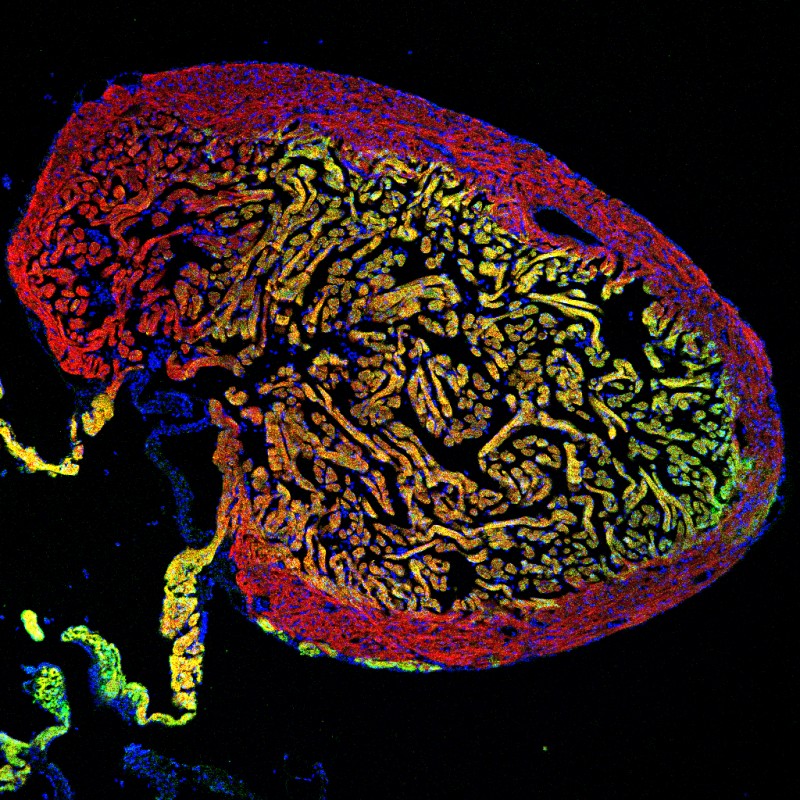

Schnitt durch ein Zebrafischherz mit zwei unterschiedlichen Muskelzellschichten (gelb und rot). Die regenerierenden Zellen des gelben Bereichs können auch zum Wiederaufbau der roten Schicht beitragen. © Institut für Anatomie, Universität Bern